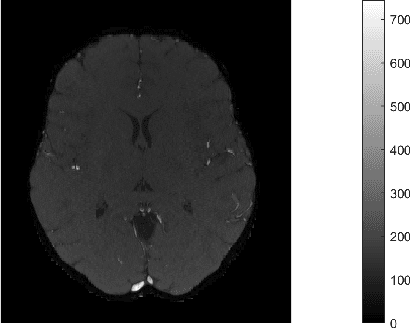

One of the most promising solutions for uncertainty quantification in high-dimensional statistics is the debiased LASSO that relies on unconstrained $\ell_1$-minimization. The initial works focused on real Gaussian designs as a toy model for this problem. However, in medical imaging applications, such as compressive sensing for MRI, the measurement system is represented by a (subsampled) complex Fourier matrix. The purpose of this work is to extend the method to the MRI case in order to construct confidence intervals for each pixel of an MR image. We show that a sufficient amount of data is $n \gtrsim \max\{ s_0\log^2 s_0\log p, s_0 \log^2 p \}$.